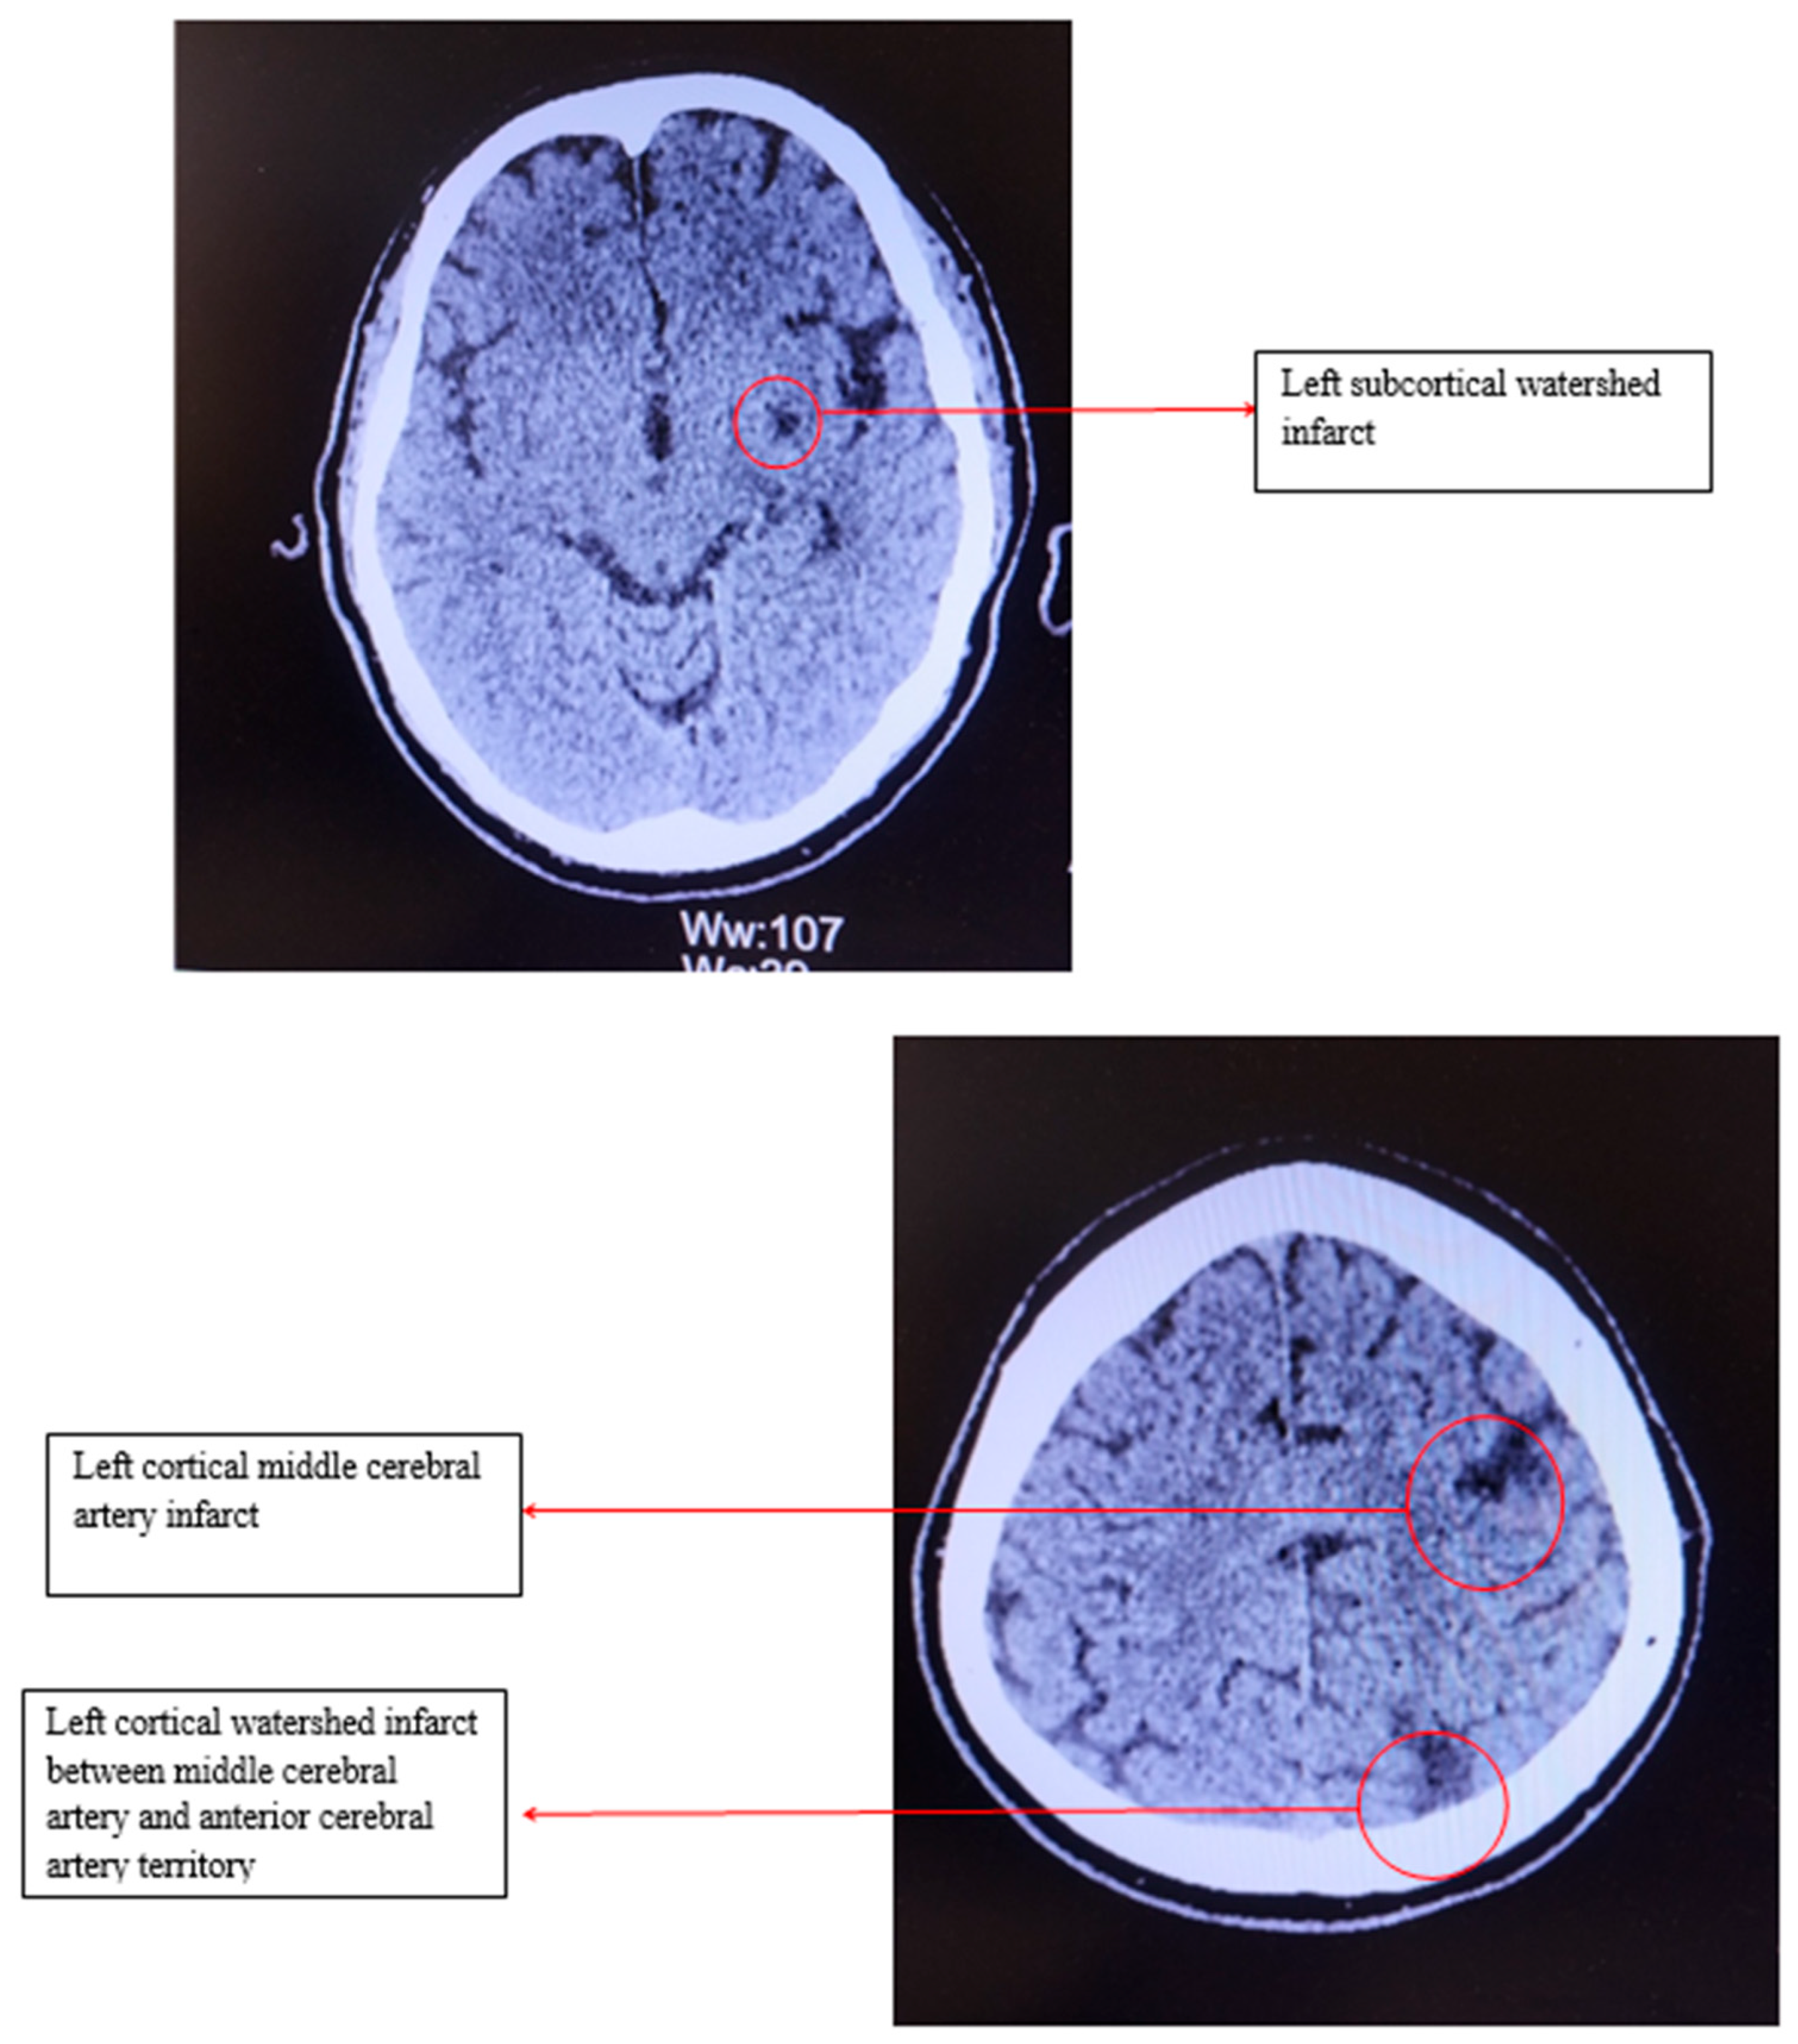

Shortly after presentation, the medical staff performed an electrocardiogram, which revealed sinus bradycardia, with a heart rate of 46bpm and no ST/T changes. Cranial computed tomography showed several chronic infarction areas in the left frontal, parietal and in the left internal capsule (Figure 1).

Figure 1. Computed tomography of the head.